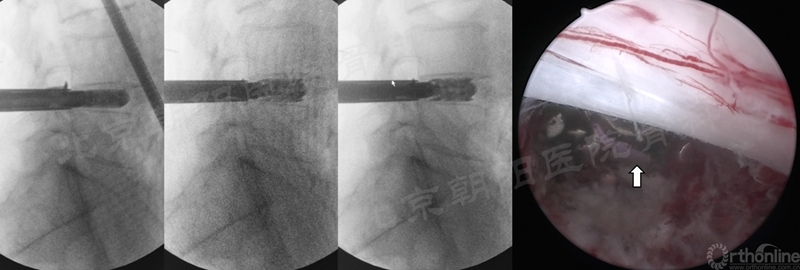

椎间隙处理

植入可撑开Cage